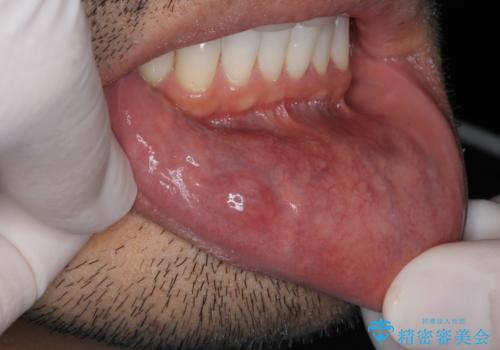

唇を噛んでしまった 粘液嚢胞の摘出

- 唇を噛んでしまい、それ以来唇が膨れ治癒しないことの改善を求めて来院されました。

マイクロスコープ下で唾液線を丁寧に摘出することで再発を防ぎます。

口の粘膜には小唾液腺という、唾液を産生する器官があります。

唾液を口腔内に排出するのパイプがふさがってしまい、唾液がうまく出ていかず漏れだした粘液が貯まってくると粘膜が盛り上がったように見えます、これが粘液嚢胞です。

下くちびるの内側や舌の裏によくみられ、一般的に痛みはありません。

マイクロスコープ下で行うことで最小限の侵襲で摘出を行い治癒も良好な状態に導くことができます。